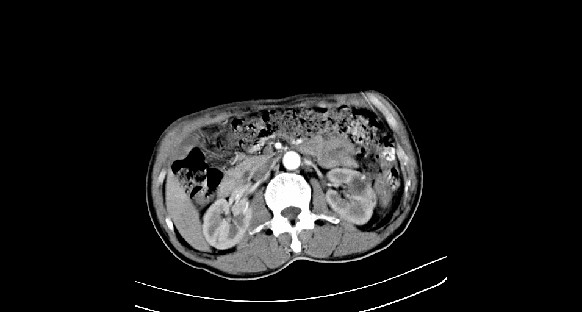

男性,70岁,体检b超发现左肾占位,请各位战友发表一下观点

左肾有两个病灶,且较大的病灶内可见点状钙化灶,增强扫描边缘也是呈渐进性强化,中央部分未见明显强化